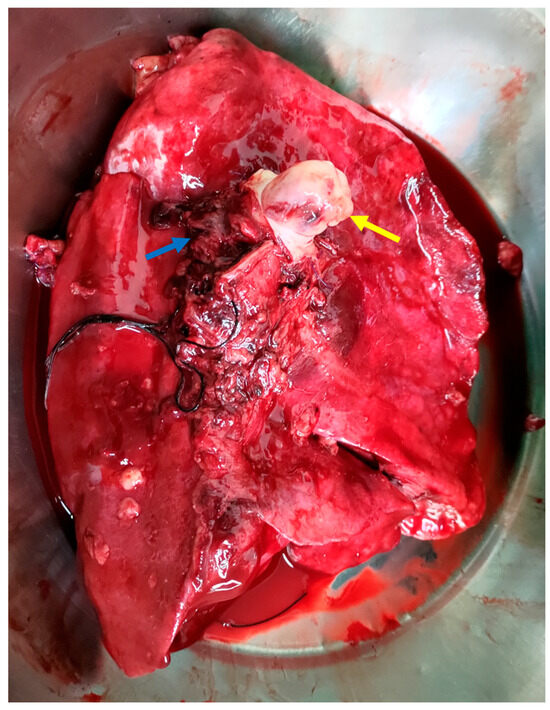

Figure 3. The intraoperative image shows tumor infiltration into the left pulmonary artery (yellow arrow), with clear involvement of the vessel wall, indicating vascular invasion. The left pulmonary veins (blue arrow) and the medially positioned trachea are also visible. This image highlights both the aggressiveness of the tumor and the complexity of the surgical resection required [7,8].